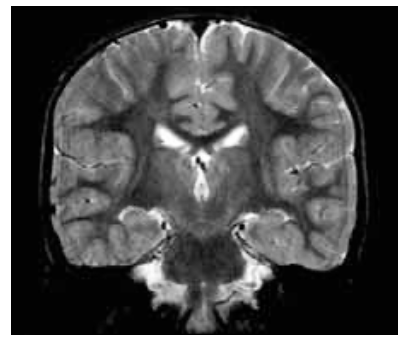

coronal (vertical)